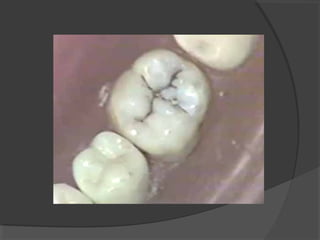

a) Class I Cavities:

Those cavities originating in anatomical pits and

fissures. They are found in the occlusal surface of

molars and premolars.

It is an infectious microbiological disease of the

teeth that results in localized demineralization and

destruction of the calcified tissues.

This is the disease that dentists deal with more than

90% of the time in operative dentistry. Several

theories were postulated concerning the cause of

caries, of these theories the acidogenic theory is

considered the most microbial enzymatic action on

ingested carbohydrates. These acids will decalcify the

inorganic portion of the teeth; then the organic portion

is disintegrated. This destructive process progresses

more rapidly in dentin than in enamel.